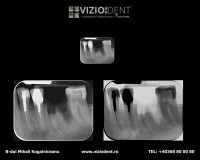

- radiografie retroalveolară

- radiografie bitewing

- radiografie ocluzală

- radiografie retroalveolară excentrică